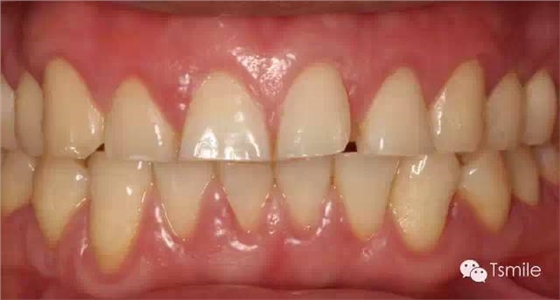

圖3 :夜磨牙導(dǎo)致的物理性磨耗

圖2: 長(zhǎng)期飲用碳酸飲料導(dǎo)致的酸蝕癥 2.磨耗面外觀特征(appearance) 物理性的磨耗形成的磨耗面邊緣尖銳、表面光滑閃亮。而酸蝕癥導(dǎo)致的磨耗面邊緣圓鈍,多呈杯狀凹陷。 3.上下頜相對(duì)牙齒的磨耗量對(duì)比(amount) 物理性的磨耗上下頜相對(duì)牙齒牙面的磨耗量基本一致。而酸蝕癥導(dǎo)致的牙列重度磨耗上下頜相對(duì)牙齒牙面的磨耗量可以完全不同,甚至一側(cè)有嚴(yán)重的磨耗而對(duì)側(cè)完全沒(méi)有磨耗。 4. 上下頜相對(duì)牙齒的磨耗面是否有咬合接觸(contact) 物理性的磨耗所導(dǎo)致的牙列重度磨耗,其上下頜相對(duì)牙齒的磨耗面之間一定有咬合接觸。而化學(xué)性酸蝕癥所導(dǎo)致的牙列重度磨耗,其上下頜相對(duì)牙齒的磨耗面之間可能完全沒(méi)有咬合接觸。